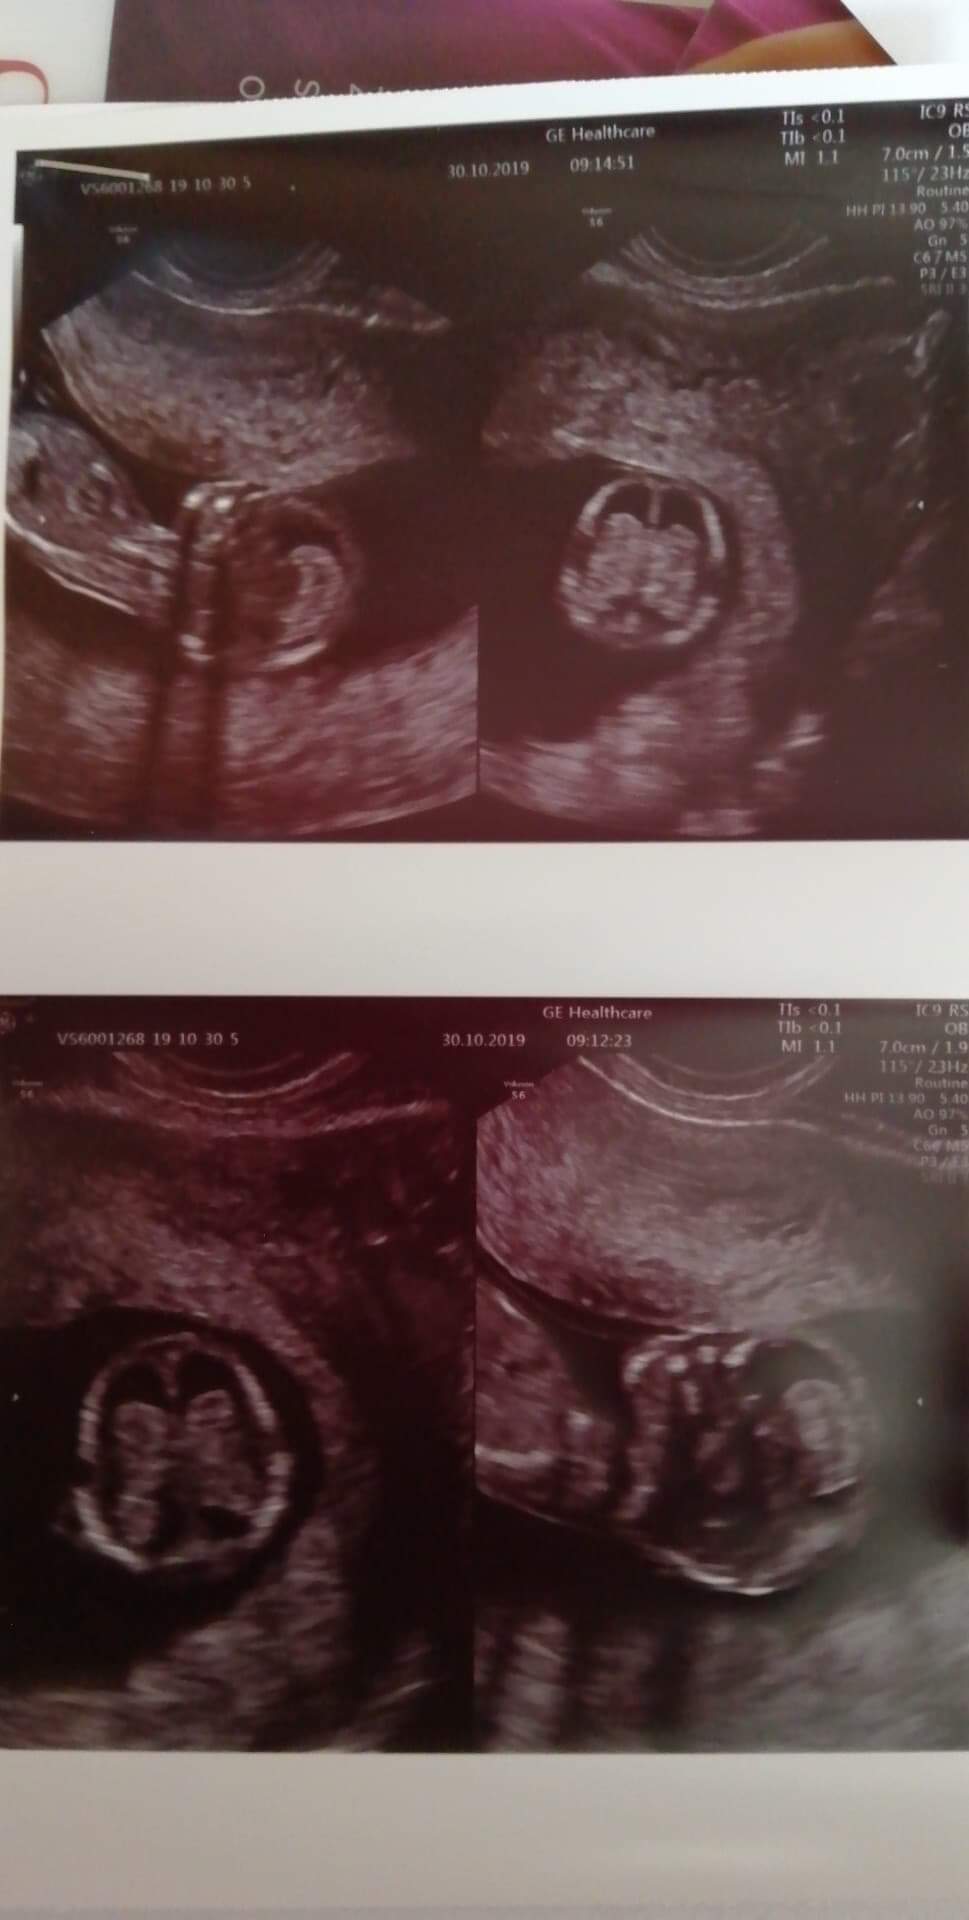

Dzień dobry wszystkim. Dziś byłam na badaniu genetycznym i lekarz mnie strasznie nastraszył że mózg dzieciątka nieprawidłowo się rozwija i kazał mi jak najszybciej zgłosić się do mojego gin żeby dał skierowanie do szpitala strasznie się boję myślicie że lekarz mógł się mylić?

Tu dołączam zdjecie